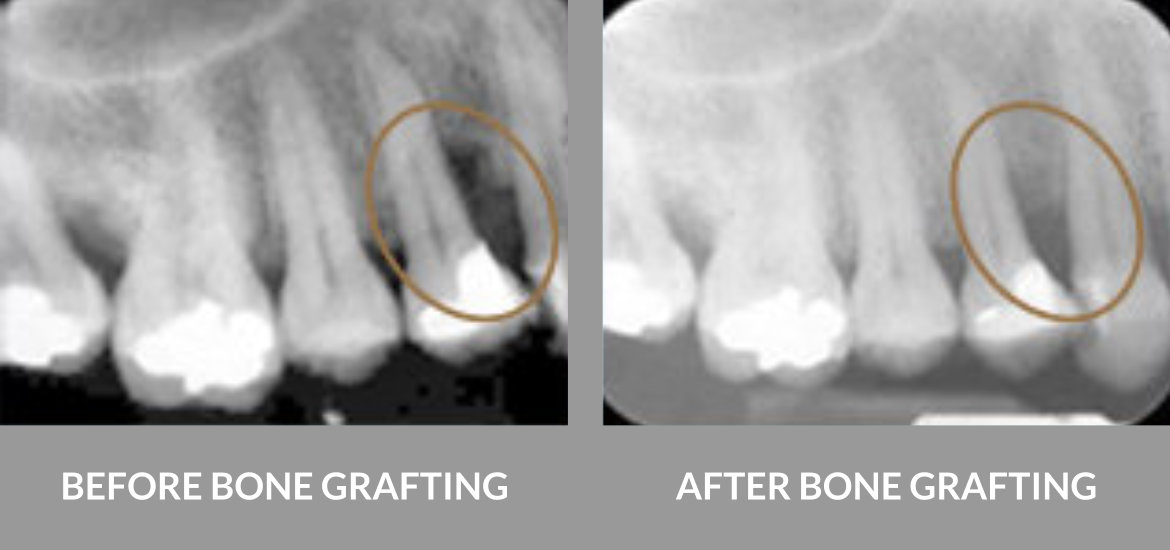

Bone Grafting

A strong jawbone is essential for successful dental implant placement. When bone loss occurs—whether from tooth extraction, gum disease, or injury—bone grafting can restore the foundation needed for implants.

Dr. Liu is highly experienced in bone grafting procedures, using advanced techniques and Piezosurgery technology to rebuild bone with precision and minimal discomfort.

Bone Grafting Procedure